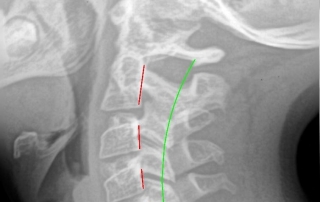

Subluxation and Disability! Adjustment is an Opportunity!

In 2013, Journal of Gerontology published study results assessing quality of life people with Subluxation visible on the side view neck x-ray. And the conclusions were: Every millimeter displacement forward from normal effects in declining [...]